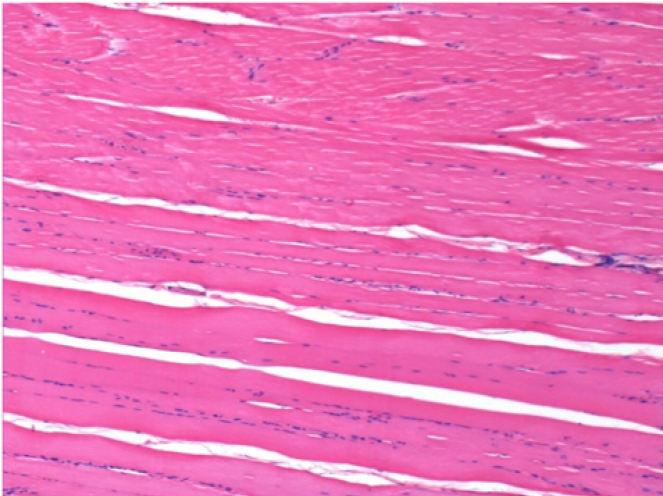

بعد 3 أشهر من حقن إندوبيل

3 أشهر (D90) بعد حقن Endopeel 0.1 مل في العضلة أمام الظنبوب اليمنى.

L : Control-100xD90

R:100xD90